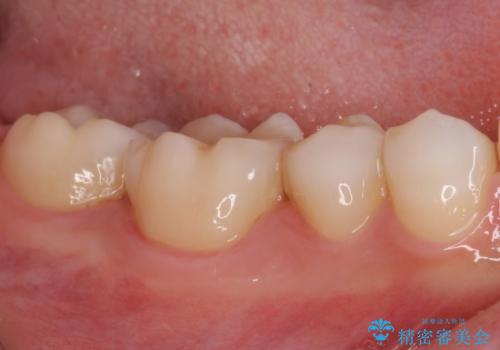

レントゲン写真などから、速やかに処置を行うべき歯が2歯あったため、それぞれセラミックインレーとPGAインレー(ゴールドインレー)にて修復治療を行うこととしました。

どちらの歯も痛みなどの症状はなく、治療後も異常所見なく経過をたどっています。

上顎大臼歯は向かい合った人から見えることはほとんどないため、切削量が少なく、適合の良いゴールドインレーが大変おすすめとなります。